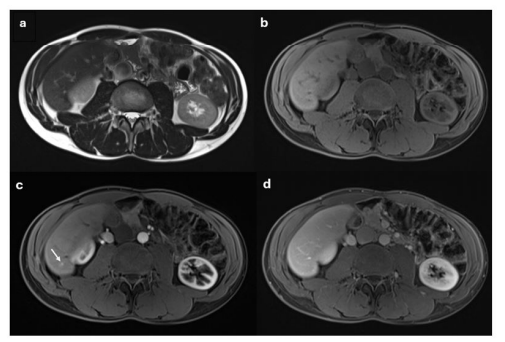

12. Vascular Endothelial Growth Factor (VEGF): Elevated by 29.7%, indicating increased vascular activity, though not all cases were malignant (Figure #1).

Circulating Tumor DNA (ctDNA): ctDNA was elevated in 16.6% of patients with LI-RADS 3 lesions. The presence of ctDNA indicated tumor-specific genetic alterations, and in these cases, the detection of ctDNA was associated with a higher likelihood of malignant transformation. Patients with elevated ctDNA were monitored more closely through imaging and clinical follow-up (Figure #2).

In patients diagnosed with LI-RADS 3 lesions, the imaging characteristics were consistent with intermediate probability for hepatocellular carcinoma (HCC). These lesions often displayed mild arterial phase hyperenhancement (APHE) without washout in the portal venous phase or capsular appearance.

Serum biomarker analysis revealed elevated AFP levels in 47.61% of patients, with a mean value of 119 ng/mL. Other elevated biomarkers included AFP-L3, GGT, and IL-6.